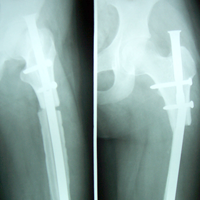

Case:5 Ewing sarcoma with implant failure

Breakage of Nail

Refixation with Angle Bladed Plate and Sever Graft

Ewing's Post Nailing and Bone Grafting

3 Months Post -Op

6 Months Post-Op